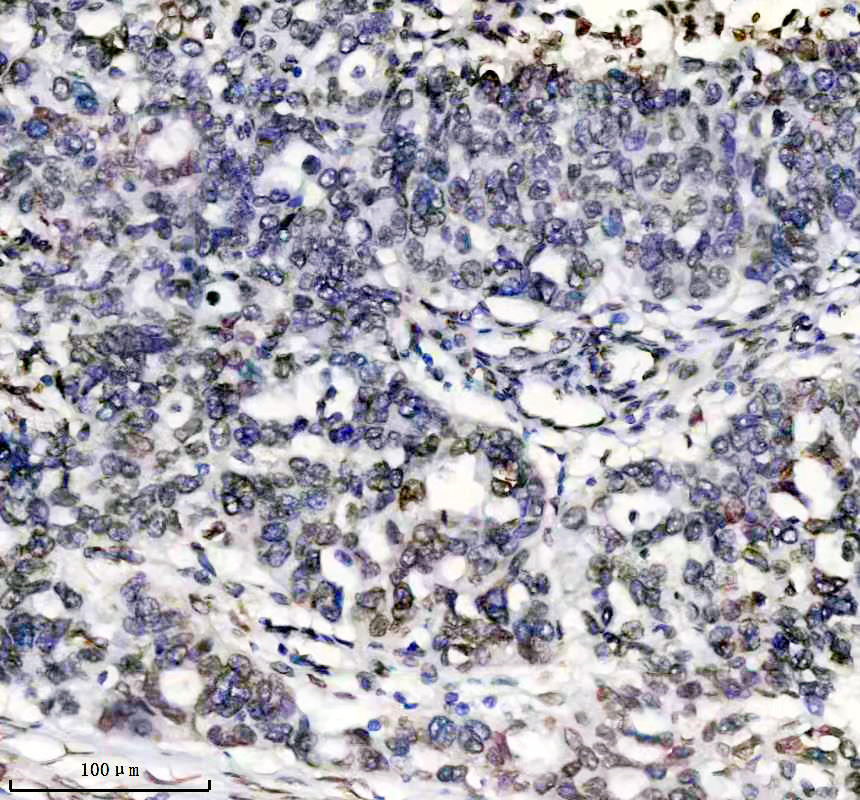

IHC analysis of Lamin A/C using anti-Lamin A/C antibody (BM4105).

Lamin A/C was detected in a paraffin-embedded section of human esophageal cancer tissue. The tissue section was incubated with rabbit anti-Lamin A/C Antibody (BM4105) at a dilution of 1:200 and developed using HRP Conjugated Rabbit IgG Super Vision Assay Kit (Catalog # SV0002) with DAB (Catalog # AR1027) as the chromogen.